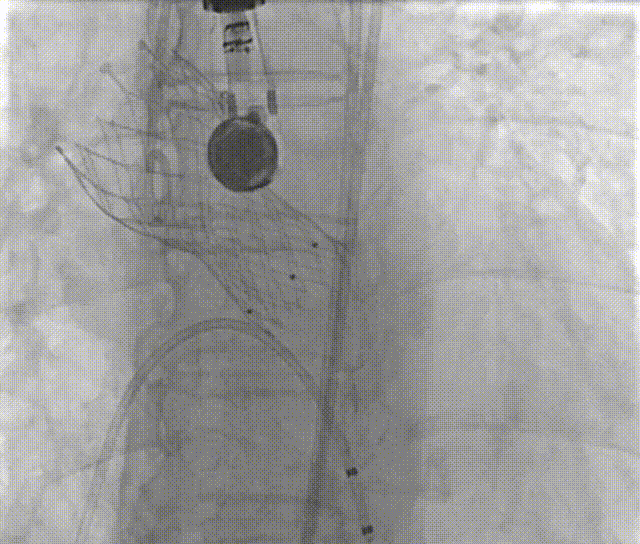

手术过程